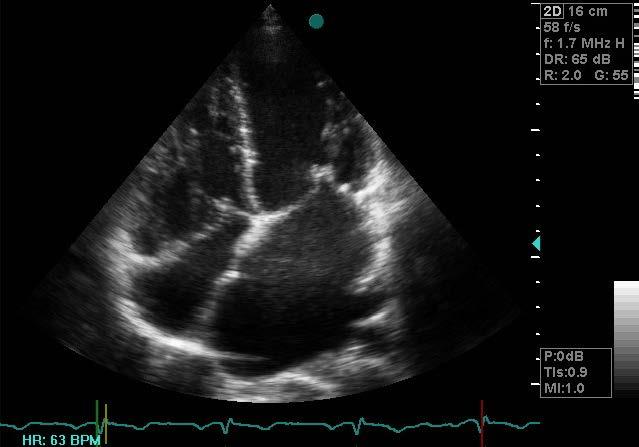

Acute rheumatic fever (ARF) and RHD develop as complications of inadequately treated strep throat or scarlet fever, both caused by infections with group A streptococcus bacteria. Ongoing inflammation accompanying ARF can cause damage to the heart valves, eventually leading to congestive heart failure, stroke, and death. Proper antibiotic treatment of initial infections and prophylactic antibiotic treatment of individuals with a history of ARF or RHD can prevent disease progression, and valve surgery can prevent and treat heart failure.